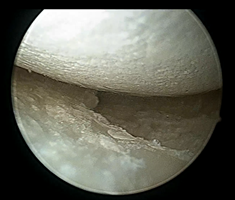

病病例病例病例二 右膝关节急性疼痛及活动受限2天入院,术中虽然明显可见痛风结晶及滑膜增生